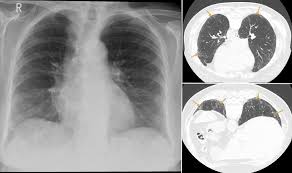

It has a fatal outcome in many cases. Most of our knowledge about imaging findings in interstitial lung disease comes from HRCT. Although rare childhood ILD chILD is associated with significant morbidity and mortality most notably in conditions.

Radiographic evidence of interstitial fibrosis consisting of a reticular pattern that involves mainly the lower lung zones is seen in only about 3 of patients who have systemic lupus erythematosus. Interstitial lung disease ILD in pediatric patients is different from that in adults with a vast array of pathologic conditions unique to childhood varied modes of presentation and a different range of radiologic appearances. By contrast interstitial abnormalities are seen in approximately 30 of patients at high-resolution CT 21 22.

Multimodality Imaging In Connective Tissue Disease Related Interstitial Lung Disease Clinical Radiology